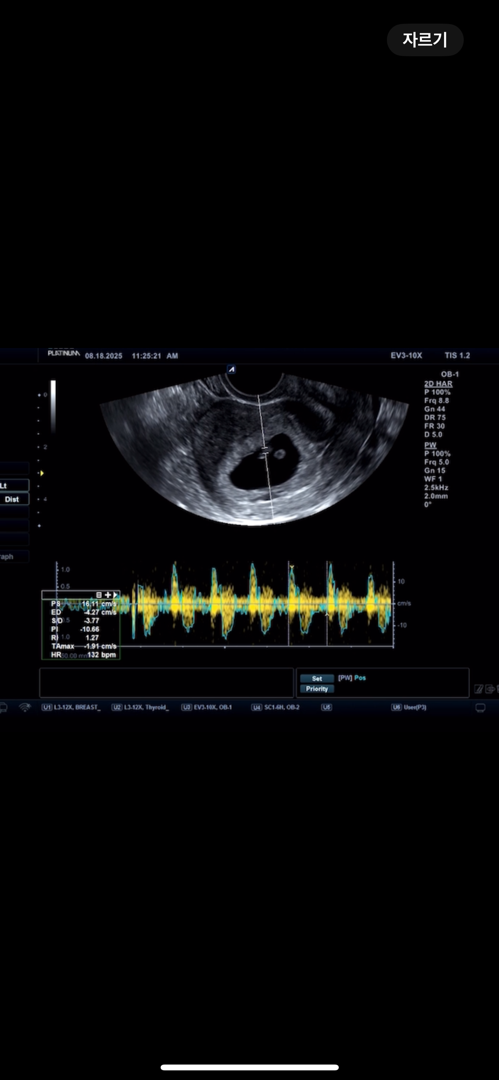

계속 갈색혈이 지속적으로 나와서 걱정하고 있던 임산부에요,, 다행히 오늘이 6주차 3일인데 아기 1주동안 좀 더 커있었구 심장소리 들었는데 140bpm 정도로 잘 뛰고 있다고 하는데 남편 눈에 그렁그렁 눈물이 ㅋㅋ ㅠㅠㅠ 심소 듣기 전이랑 후 마음이 정말 다르네요

아뇨 질 초음파로 했어요! 감사합니다 ㅎㅎ 네 대충 6주 3일 ~ 7주 정도로 추산하시더라구요 ! 🥰